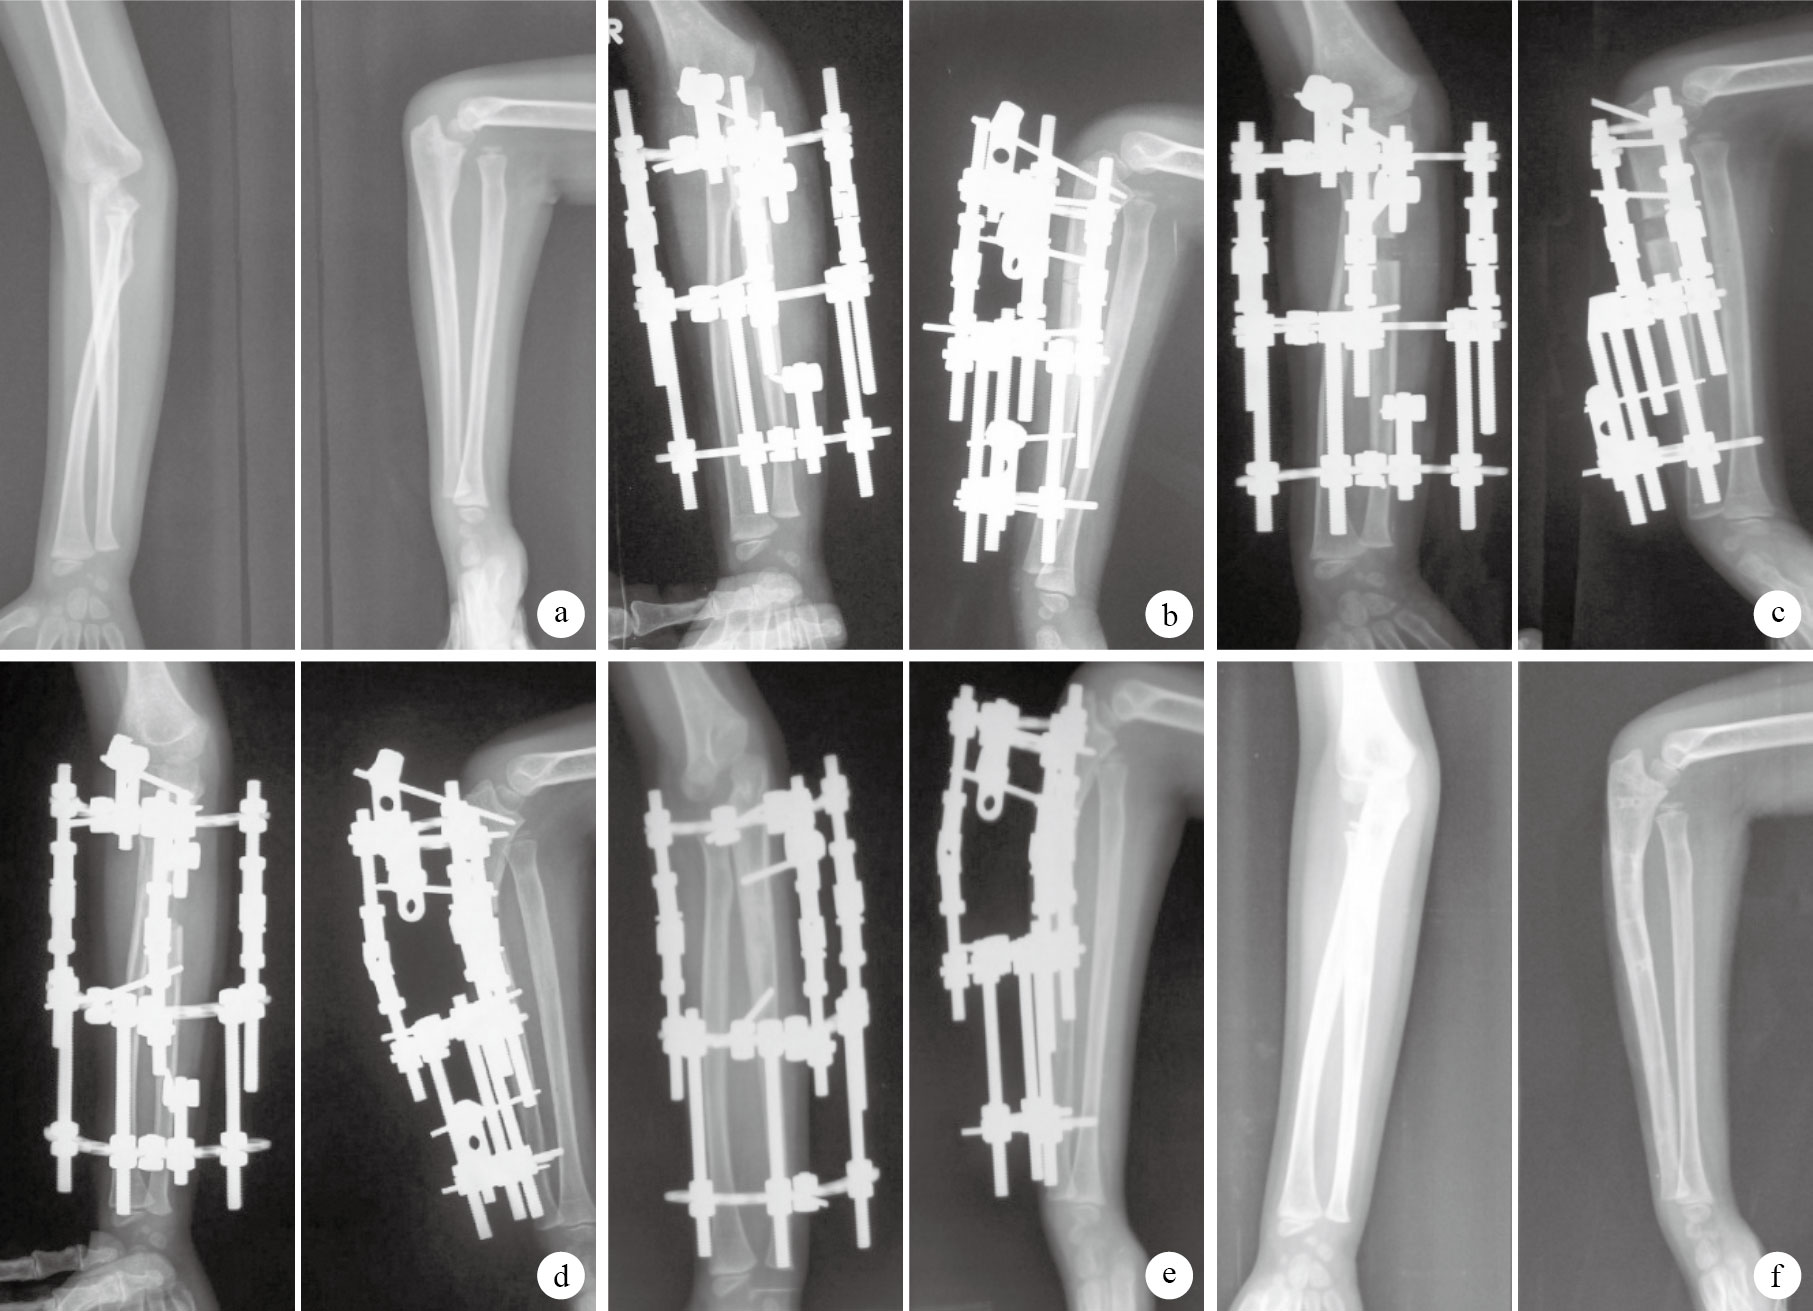

本組均采用改良Ilizarov半環形外固定架(北京骨外固定技術研究所)。術前將半環形外固定器與螺紋桿、關節鉸鏈和螺紋針組裝成可調節、變向的三維立體外固定架,背側鉸鏈需與既定尺骨成角延長方向一致。全麻下,取2.5 mm螺紋針將外固定架固定于前臂尺骨背側(圖 1 a)。然后距尺骨鷹嘴5~7 cm處,沿尺骨嵴作長1.0~1.5 cm縱切口,剝離骨膜,以微創截骨器行尺骨橫斷截骨(圖 1 b)。最后關閉切口。

術后第3天開始肘關節伸屈及前臂旋轉功能鍛煉。第7天開始行尺骨縱向延長,每天1 mm,分6 次完成。定期攝肘關節正側位X線片,觀察肱橈關節間隙達約5 mm時,調整半環形外固定架3 組鉸鏈開始不等距延長。本組于尺骨縱向延長8~11 d,平均9 d后開始不等距延長;此時尺骨縱向延長8~11 mm,平均8.6 mm。

根據Bado分型結果選擇不同不等距延長方法:Ⅰ型,背側鉸鏈延長1 mm/d,分6次完成;其余兩側鉸鏈延長0.5 mm/d,分3次完成;使尺骨向橈骨小頭脫位相反方向成角,隨著所成角度增大,橈骨小頭在骨間膜的牽拉作用下緩慢復位。待影像學觀察橈骨小頭復位后,停止尺骨延長。12例Ⅰ型患兒尺骨不等距延長10~14 d后橈骨小頭復位,平均12 d;此時尺骨向背側成角15~20°,平均 16.7°。待尺骨截骨區骨性愈合后,去除外固定架,無需支具外固定。

Ⅲ型,后內側鉸鏈延長1 mm/d,分6次完成;其余兩側鉸鏈0.5 mm/d,分3次完成;使尺骨向后內側成角,隨著所成角度增大,橈骨小頭緩慢復位;影像學觀察橈骨小頭復位后,停止尺骨延長。2例Ⅲ型患兒尺骨不等距延長11、13 d后橈骨小頭復位;此時尺骨向后內側成角15、17°。待尺骨截骨區骨性愈合后,去除外固定架,無需支具外固定。

本組手術時間50~65 min,平均58 min。患兒均獲隨訪,隨訪時間6~33個月,平均21個月。均無切口、釘道感染和骨化性肌炎、橈骨小頭再脫位發生。X線片復查示,術后82~114 d(平均90 d)尺骨截骨區骨性愈合,去除外固定架,肱橈關系佳(圖 2)。肘關節伸屈和前臂旋前、旋后活動度較術前均明顯改善,比較差異有統計學意義(P<0.05)。見表 1、2。末次隨訪時,根據Mackay等功能評定標準進行療效評價:獲優12例,良2例。